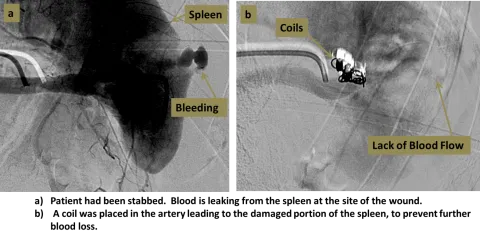

- Imaging: Bedside FAST scan for quick assessment; CT angiography is gold standard for localizing the bleed.